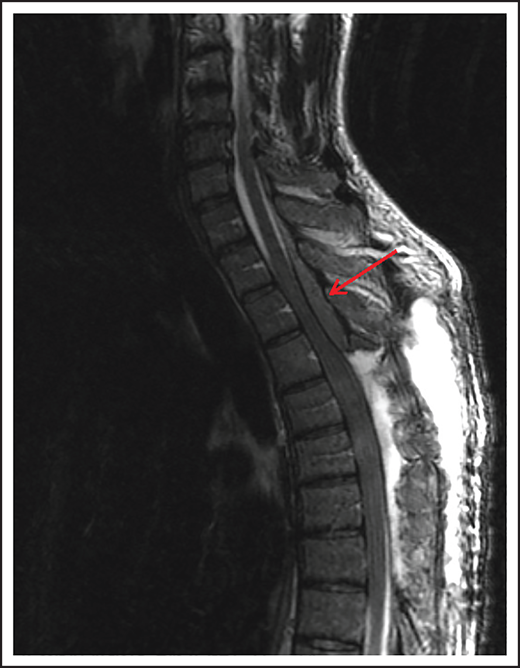

Spinal cord compression can cause severe and permanent neurologic deficits and must be diagnosed and treated emergently to reverse symptoms and prevent devastating sequelae. Epidural lesions caused by lymphoma involvement of the vertebral bodies of the spine or paravertebral lymph nodes can lead to spinal cord compression (Figure 2). In a retrospective study of 131 patients with primary bone lymphoma, one-third of the patients had involvement of the spine leading to cord compression in half of them.11 Most patients present with back pain, although neurologic symptoms including paralysis, sensory loss, and bladder and bowel dysfunction can evolve rapidly. Delayed diagnosis and treatment can result in permanent neurologic deficits. Diagnosis is typically made with MRI of the spine. Dexamethasone can improve neurologic symptoms and signs until definitive treatment, including chemotherapy and/or radiation can be instituted. Occasionally, patients may need neurosurgical intervention to maintain stability of the spine.

MRI of the cervical and thoracic spine of a patient with epidural spinal cord compression. A sagittal T2 image shows epidural involvement by NHL with compression of the underlying spinal cord.